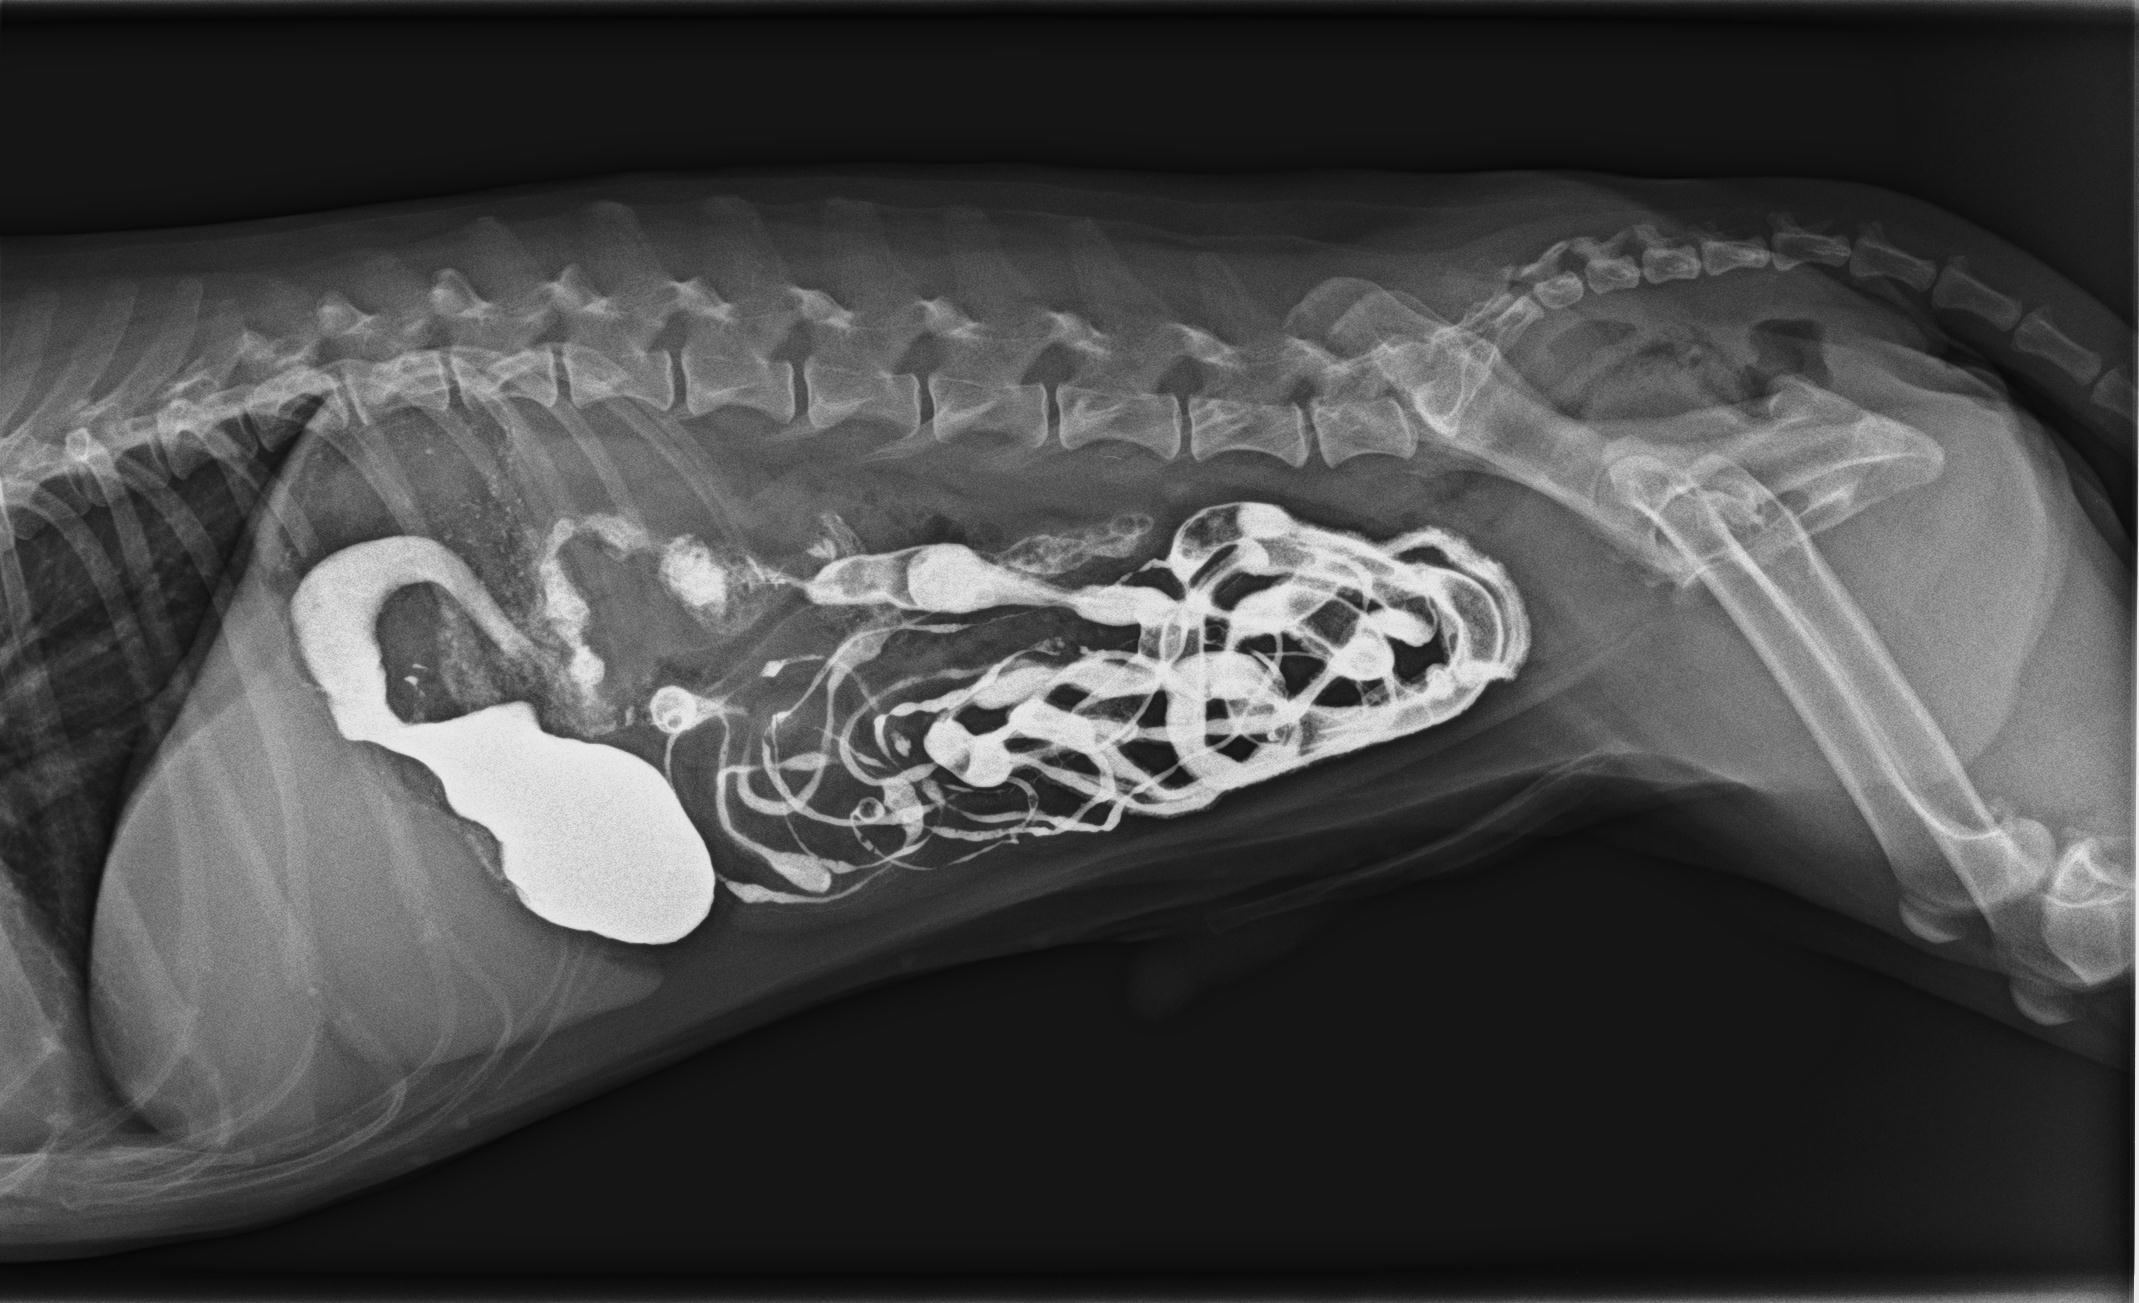

Ja, Bobby ging es sichtlich schlecht, so matt er auf meinem Behandlungstisch herumlag, ohne Interesse an Leckerlis oder anderen Dingen. In seinen Därmen rumorte es, sein Magen gluckerte, und bei dem Abtasten des Abdomens zeigte er deutliche Bauchschmerzen. Die mitgebrachte Kotprobe war dünnflüssig, mit Schleim und Blut überzogen und stank fürchterlich. Um Bobby zu helfen, musste ich erst einmal herausfinden, wie ernst die Lage war. War er schon dehydriert? Hatte er möglicherweise doch einen Fremdkörper aufgenommen? Oder waren Parasiten oder Giardien verantwortlich für den Durchfall?